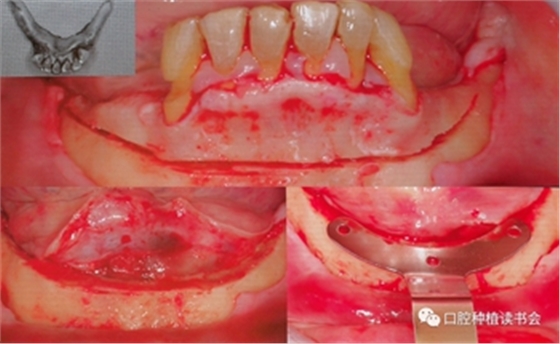

周?chē)?guó)輝教授分享了多例精彩的Trefoil下頜無(wú)牙頜種植修復(fù)案例,我們一起分享其中一例。該患者下頜牙列缺損,余留牙松動(dòng)3度,術(shù)前完成影像學(xué)檢查、排牙分析與打印3D頜骨模型,根據(jù)Trefoil的要求,種植修復(fù)體切牙切緣到骨水平的距離不應(yīng)小于22mm,為什么要保證足夠的修復(fù)空間呢?主要是因?yàn)門(mén)refoil使用的是樹(shù)脂與金屬支架混合型修復(fù)體,而且是正式的修復(fù)體。

該患者的下頜牙槽嵴頂為刃狀,Trefoil理念的手術(shù)要求:必須修整出足夠?qū)挾鹊钠脚_(tái),便于修復(fù)及義齒的維護(hù),骨修整線必須兩側(cè)頦孔上方,修整后形成不小于7mm寬度的骨平臺(tái)(種植體兩側(cè)最小保留1mm骨壁)(圖6)。

圖6 下頜骨修整線,修整后安裝定位導(dǎo)板

使用超聲骨刀完成骨修整后,使用導(dǎo)板確認(rèn)是否滿足種植體植入條件,然后使用球鉆定點(diǎn),2mm先鋒鉆預(yù)備后,測(cè)量垂直高度,以確定是否滿足22mm修復(fù)空間的要求。在定位導(dǎo)板上,先預(yù)備中間種植窩,逐級(jí)預(yù)備,根據(jù)患者條件確認(rèn)最后鉆的寬度,植入錐度連接的軟組織水平、平行壁植體,該種植系統(tǒng)是有11.5和13mm的不同長(zhǎng)度,以及 4.5和6mm 高度的光滑頸環(huán)平行壁的軟組織水平種植體。(圖7)